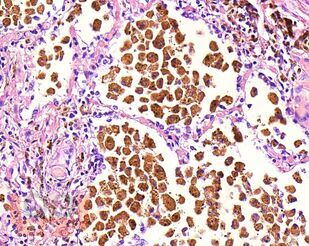

В учебном пособии представлен теоретический материал, перечень макропрепаратов и микропрепаратов, демонстрирующих типовые проявления патологических процессов. В цветных иллюстрациях и в описании микропрепаратов cделан акцент на наиболее важных гистологических изменениях, позволяющих на светооптическом уровне диагностировать и дифференцировать состояния, отклоняющиеся от нормы, в том числе с использованием различных гистологических окрасок. Пособие помогает выделить главные аспекты изучаемых патологических процессов, организовать и конкретизировать учебный процесс.